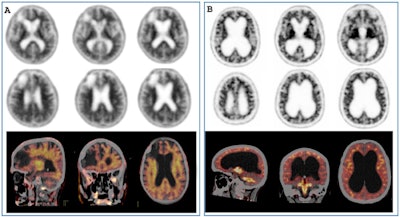

![(A) [F-18] FDOPA PET image of a healthy patient (A.1) and a patient with Parkinson's disease (A.2). B: Pitfalls and artifacts in presynaptic dopaminergic imaging. [F-18F] FDOPA PET scan (B.1) of a patient with suspected Parkinson's disease showing a decrease in the right putamen. However, the PET/MRI image (B.2) shows that the decreases are due to the artifact of spaces surrounding the walls of vessels within the brain parenchyma observed on MRI.](https://img.auntminnieeurope.com/files/base/smg/all/image/2025/02/2025_02_13_mol_insider_Figure_6.67ad30a73f2ff.png?auto=format%2Ccompress&fit=max&q=70&w=400) (A) [F-18] FDOPA PET image of a healthy patient (A.1) and a patient with Parkinson's disease (A.2). B: Pitfalls and artifacts in presynaptic dopaminergic imaging. [F-18F] FDOPA PET scan (B.1) of a patient with suspected Parkinson's disease showing a decrease in the right putamen. However, the PET/MRI image (B.2) shows that the decreases are due to the artifact of spaces surrounding the walls of vessels within the brain parenchyma observed on MRI.

(A) [F-18] FDOPA PET image of a healthy patient (A.1) and a patient with Parkinson's disease (A.2). B: Pitfalls and artifacts in presynaptic dopaminergic imaging. [F-18F] FDOPA PET scan (B.1) of a patient with suspected Parkinson's disease showing a decrease in the right putamen. However, the PET/MRI image (B.2) shows that the decreases are due to the artifact of spaces surrounding the walls of vessels within the brain parenchyma observed on MRI.